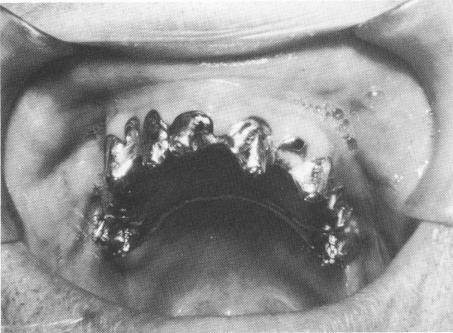

Fig. 10-247. The template was then fitted in the mouth. (From Linkow, L. I.: Prefabricated endosseous implant prostheses, Dent. Concepts 10 [3] :2-10, 1967.)

vertical extensions of the template so that they were flush with it (Fig. 10-246). The template was tried in the patient's mouth (Fig. 10-247), and the small set screws were inserted through the template and into the internal threads of the implants (Fig. 10-248).